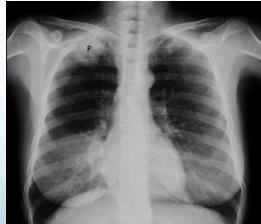

- Compression causes:

- Growing tumors (e.g., Pancoast tumor)